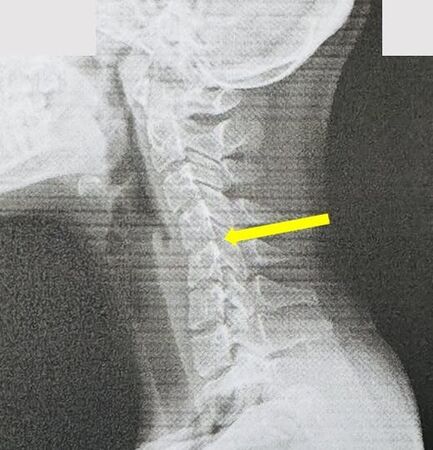

20歲女大生長期頭痛、頸部痠痛僵硬到神經內科求診,檢查發現頸椎弧度消失,呈現「僵硬直線」甚至有滑脫的情況,顯示頸椎正提前退化,程度有如60歲的中老年人。醫師指出,這是俗稱的「手機頸」,由於患者平常習慣長時間滑手機,此時頸椎承重等同脖子掛著一顆保齡球,長期下來導致變形與退化的發生,也提醒可以透過3個方式減少低頭傷害。

收治個案的員榮醫院神經內科主任葉宗勳指出,健康的頸椎應有自然的「C字形」弧度,能分散頭顱重量與活動壓力,猶如天然避震器。然而該名患者平時習慣長時間滑手機、追劇,甚至常常手拿手機躺在床上邊看邊睡著,睡姿不良,導致頸椎長期承受過大壓力,出現變形與退化。

葉宗勳表示,頸椎變直會帶來一連串後果,如頑固性頭痛、頭暈,頸椎錯位影響腦部血流,壓迫臂叢神經,導致肩膀、手臂、手指麻木刺痛,也可能提前數十年面臨椎間盤突出、骨刺問題。此外,長期不良姿勢會對頸椎及周圍肌群造成慢性壓力,進而影響頸部神經傳導功能,引發頭痛、手麻、眩暈等症狀。